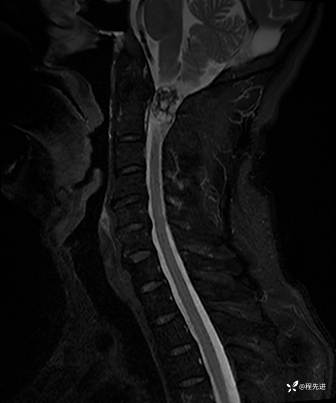

T1: